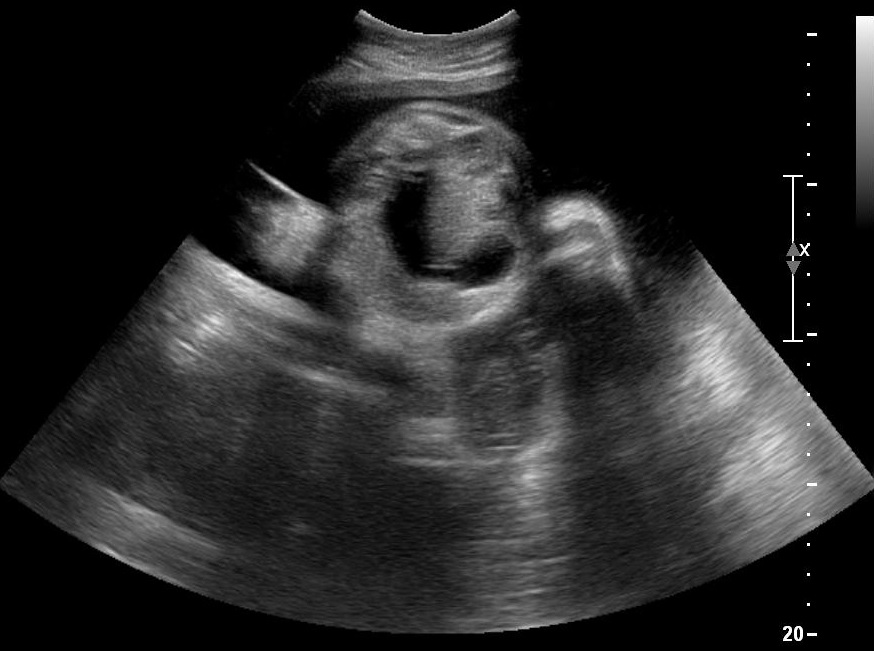

- To exclude the distance between your ultrasound probe and your region of interest, zoom in. Usually pushing the zoom button increases the image quality. On the contrary turning it zooms in without changing the frame rate, thus we suggest pushing instead of turning. Your region of interest should take up 3/4 of the whole ultrasound image.

Your image should now be adequate. Care to detail will help you make accurate measurements and provide better patient care.